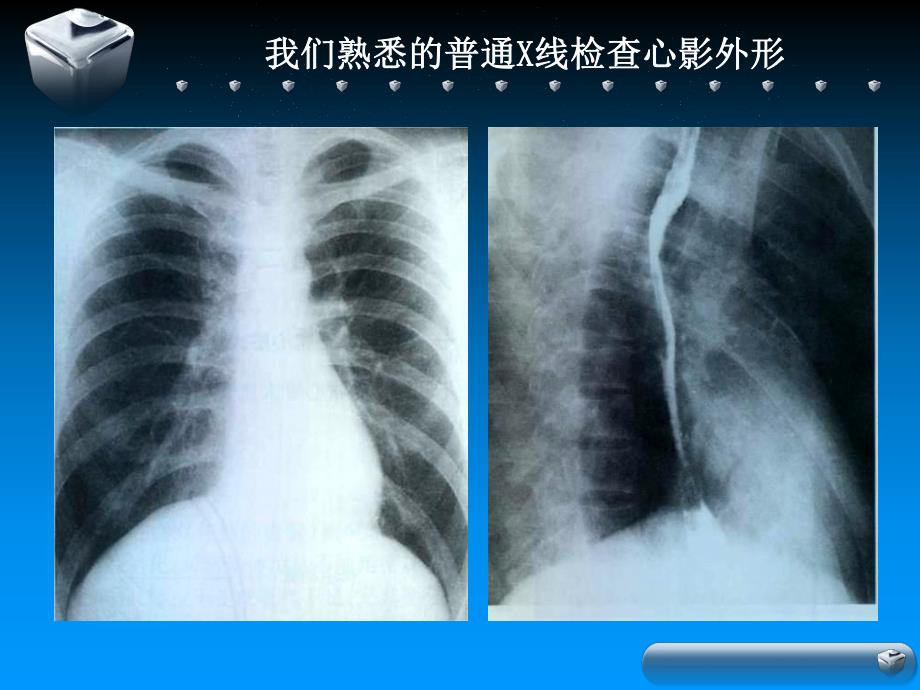

1、一、不同影像技术对术对心血管疾病的诊断诊断价值值 我们熟悉的普通我们熟悉的普通X X线检查心影外形线检查心影外形提供了直观的解剖信息提供了直观的解剖信息左室增大右室增大左房增大右房增大 冠状动脉粥样硬化性心脏病冠状动脉粥样硬化性心脏病 CT平扫时,钙化的粥样硬化斑块表现为沿房室沟平扫时,钙化的粥样硬化斑块表现为沿房室沟或室间沟走行的致密斑条状影。为诊断提供了简单的病或室间沟走行的致密斑条状影。为诊断提供了简单的病理信息。理信息。冠心病USG表现现冠状动状动脉粥样样硬化性心脏脏病心血管造影可直接显示冠脉。完成定量诊断,心血管造影可直接显示冠脉。完成定量诊断,并为治疗方案的确定提供可靠的依据并为治